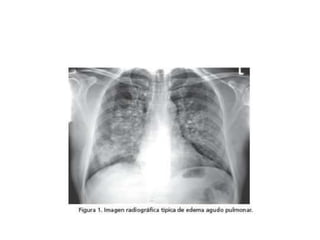

Signo de ala de mariposa (edema

pulmonar)

Patrón alveolar difuso EDEMA

PULMONAR

PULMONAR(Distress)